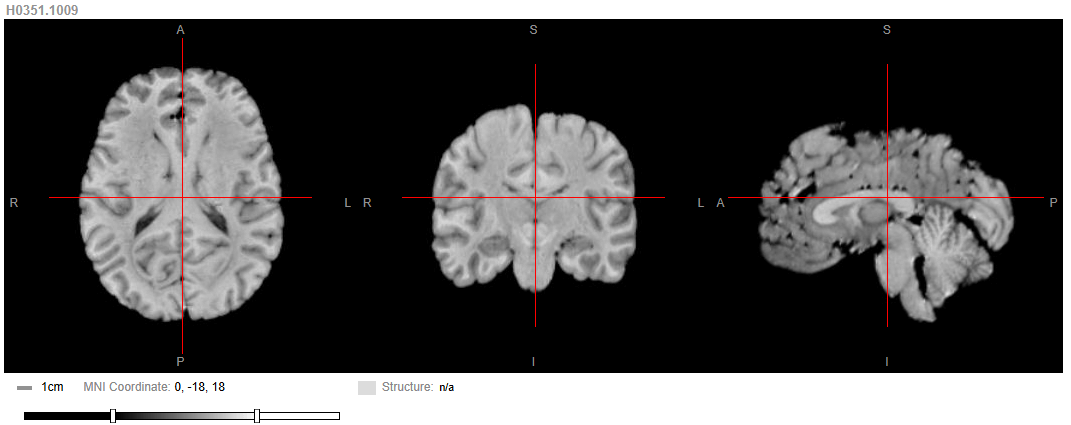

The Allen Human Brain Atlas has an online viewer for magnetic resonance (MR) imaging data to view specimens contained in the atlas. MR and diffusion tensor imaging data is also available in downloadable TAR Archive files (.tgz) through the NIH BrainSpan Project, with detailed descriptions of data acquisition in the Technical Whitepapers. The links below will prompt for file download.

- 3T structural MRI (47MB)

- 7T structural MRI (5GB)

- 3T 1200 micron diffusion (880MB)

- 3T 900 micron diffusion (1GB)